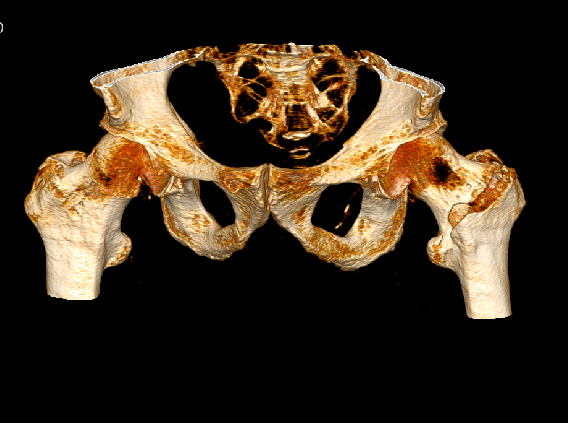

影像资料:

髋部CT+骨三维

诊 断:

左股骨粗隆间骨折(Evans Ⅱ);三度房室传导阻滞。